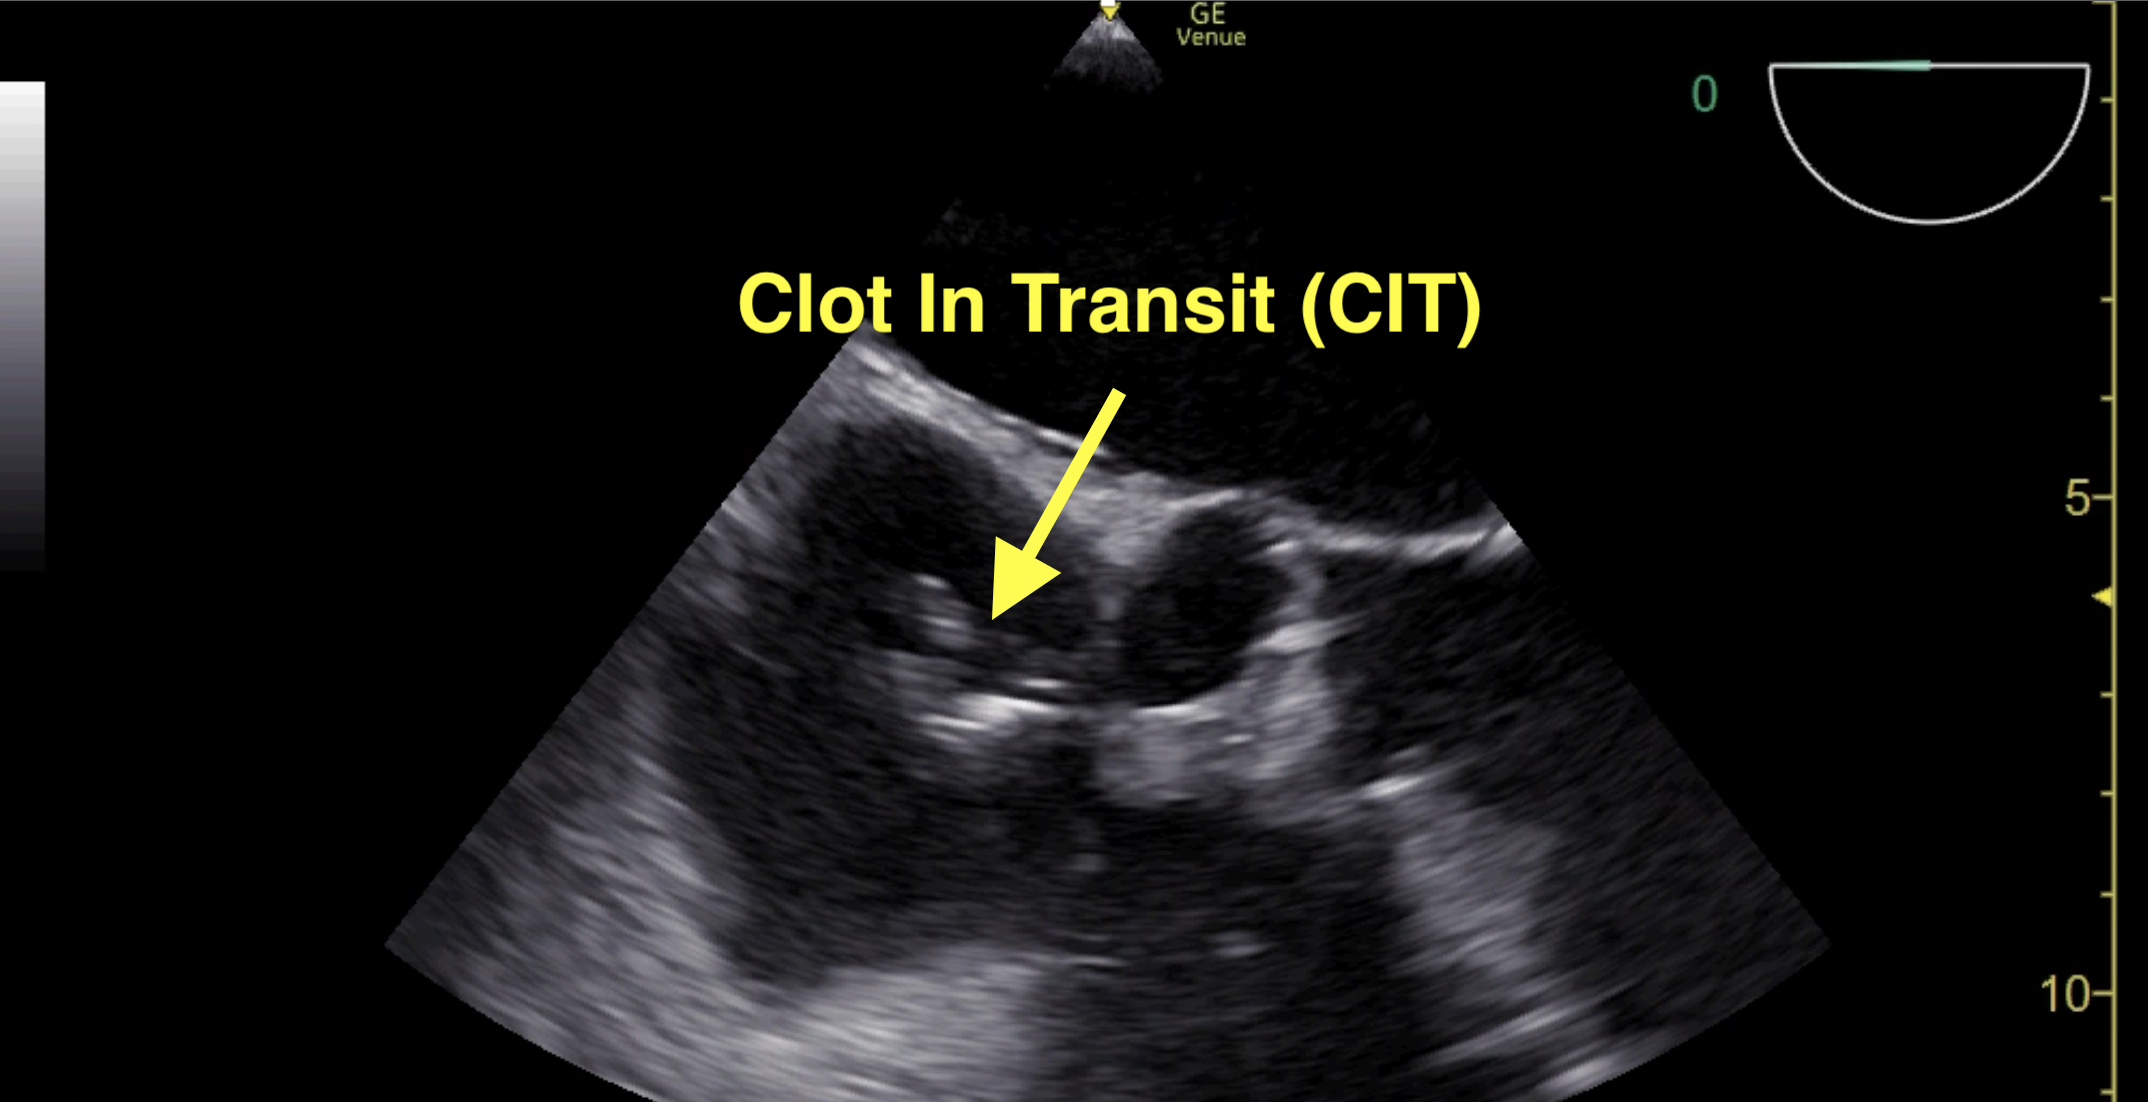

Abstract Body: Background: Pulmonary Embolism (PE) is the third leading cause of death in the United States, with mortality rates reaching 50-70% in high-risk PE and cardiac arrest-related PE, respectively. Survival in these patient populations depends on recognizing highly sensitive and specific signs of high-risk pulmonary embolism. The prevalence of clot-in-transit (CIT) ranges from 1-4% in low-risk PE but increases to over 18% in high-risk PE. CIT is highly specific (99%) for diagnosing PE and is associated with increased mortality when combined with RV dysfunction. Transesophageal echocardiography (TEE) offers unique and high-quality views of the RA-IVC and SVC junction, RV, pulmonary artery, and bifurcation to evaluate CIT and PE in cases of shock and cardiac arrest, where computed tomography pulmonary angiography is not feasible. This study seeks to determine the incidence and clinical impact of acute RV systolic dysfunction and CIT detected by TEE in patients post-cardiac arrest and in undifferentiated shock.

Results: Among the 61 patients who underwent TEE, acute RV systolic dysfunction was identified in 31% (19/61) of cases. CIT was detected in 5% (3/61) of these patients, with all of them also exhibiting RV dysfunction. All patients with CIT received thrombolysis. Notably, early and mid-systolic notching and low RVOT velocity-time integral (VTI) was present in all cases involving CIT. None of the patients presenting with CIT survived to hospital discharge.

Conclusions: TEE plays a crucial role in the detection of acute RV systolic dysfunction and CIT in patients post-cardiac arrest and in undifferentiated shock. The presence of CIT, particularly when associated with early or mid-systolic notching or low RVOT VTI, indicates a severe and high-risk clinical scenario with high mortality requiring immediate therapeutic intervention. Further studies are needed to evaluate significance of this findings in large patient populations.